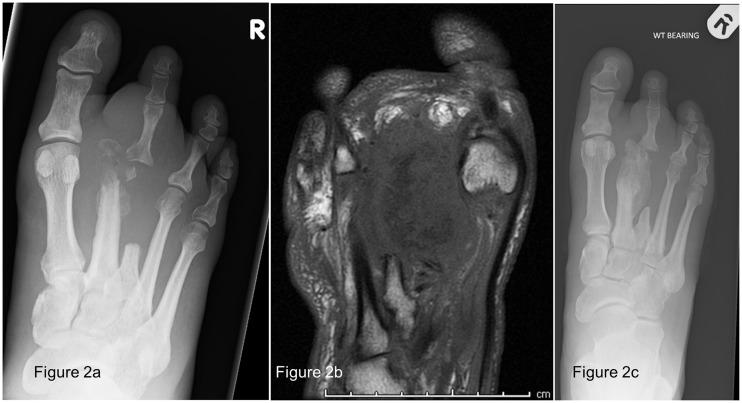

We review the literature surrounding Myositis ossificans, and describe three cases of Myositis ossificans following foot surgery in people with diabetes. All of the imaging was consistent with the descriptions of Myositis ossificans reported elsewhere in large muscle groups. These are the first reports of Myositis ossificans occurring in the feet of people with diabetes.

我们回顾了有关骨化性肌炎的文献,并描述了三例糖尿病患者足部手术后发生骨化性肌炎的病例。所有影像学表现均与其他地方报道的大肌肉群中骨化性肌炎的描述一致。这些是糖尿病患者足部发生骨化性肌炎的首例报道。